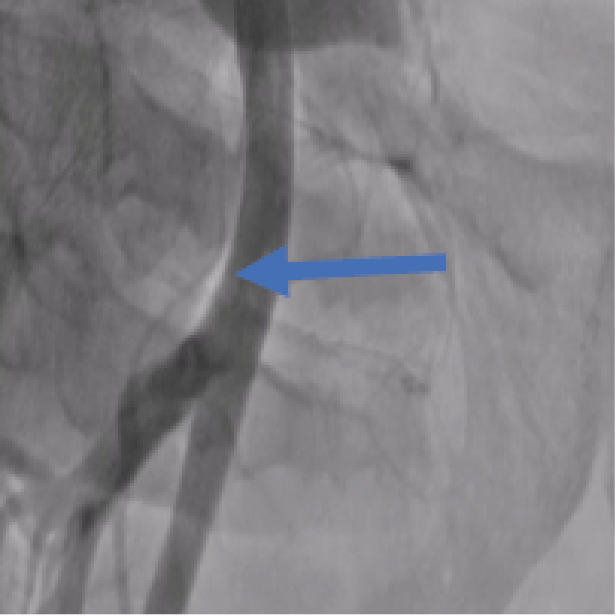

A 42-year-old male who underwent angiography with no obstructive disease found. he was discharged home on the same day but returned to the hospital for Symptoms in- clude groin swelling, unusual pain, bruising, skin changes, neuropathy from femoral nerve compression and claudica- tion from embolization or arterial compression. On examina- tion pulsatile mass in his right groin with a bruit. Angio CT suggested large pseudoaneurysm 7x8 cm in right femoral artery [figure1]. Angiography to his right common femoral artery revealed large pseudoaneurysm [2]. With a contra- lateral sheath placed in the left common femoral artery, the pseudoaneurysm was entered through the neck using 0.014 inch coronary wire. A micro introducer needle was then used to enter the pseudoaneurysm A 0.014-inch wire was then ad- vanced through the neck of the pseudoaneurysm retrograde- ly into the external iliac artery. The micro introducer sheath was then advanced into the pseudoaneurysm over the wire and retrogradely into the external iliac artery. The 0.014-inch wire was exchanged with a 0.035-inch Whole wire. The star closure device was then deployed with the anchor against the pseudoaneurysm neck with subsequent thrombosis of the pseudoaneurysm [figure 3]. Control Angiography through the contralateral sheath showed complete occlusion of the neck with no compromise to the common femoral artery.

Figure 2: Selective Angiography: Pseudoaneurysm in Right Femoral Artery